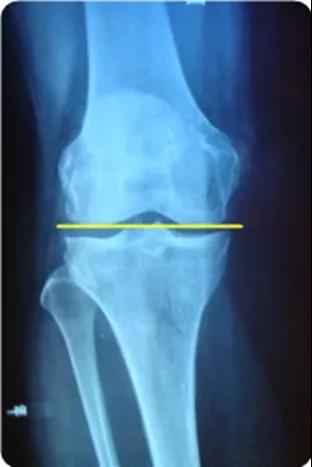

▶▶关节线

- 在膝关节X光正位片上,经胫骨平台关节承重面与股骨内外侧髁远端接触的一条直线。